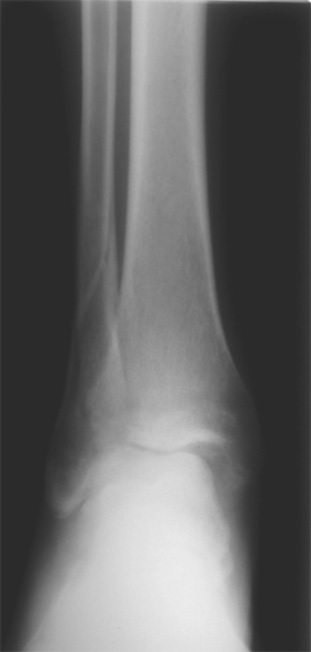

Здесь представлено решение похожей проблемы. Больной в течение года лечился консервативными мерами, и боли в голеностопе были основным показанием к операции.

Проведена обычная стандартная процедура по исправлению неудовлетворительного состояния голеностопного сустава, где кроме удлинения малоберцовой с применением compression tension device за проксимальный конец пластины, проведено замещение трикортикальным графтом из крыла, освобождение синдесмоза и медиальной щели от

фибротических масс с фиксацией.